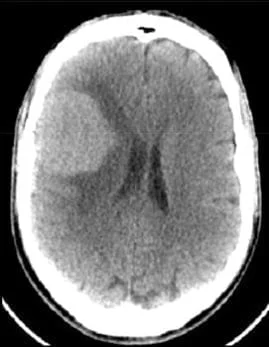

Un méningiome peut être diagnostiqué au scanner où il apparaît comme une masse ronde à la périphérie du cerveau, avec un épaississement de l’os au niveau de sa base d’insertion sur la méninge.

Il est plus fréquemment retrouvé sur une IRM sous forme d’une masse “blanche” après injection du produit de contraste intraveineux et entourée d’un œdème. Les méningiomes peuvent se rencontrer dans différentes localisations intra-crâniennes, plus ou moins facilement accessibles et qui conditionneront la technicité et les risques du geste qui vous sera proposé par votre chirurgien.

frontal droit